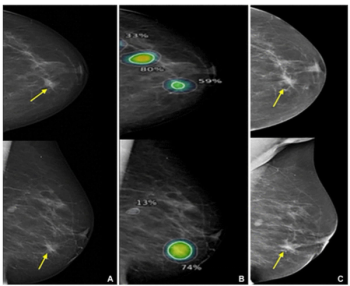

Identifying over 23 percent of interval breast cancers with a 96 percent sensitivity in mammography interpretation, an emerging AI software also facilitated correct localization in over 75 percent of cases involving interval breast cancer, according to new research.